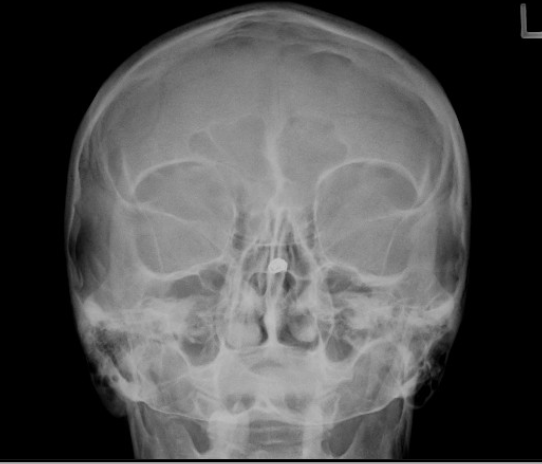

10

Q

what should be corrected about the petrous ridges in this PA cadwell

A

nothing!

11

what are the corrections for this PA caldwell (3)

CP needs to be raised

nose to go right slightly

vertex to go left